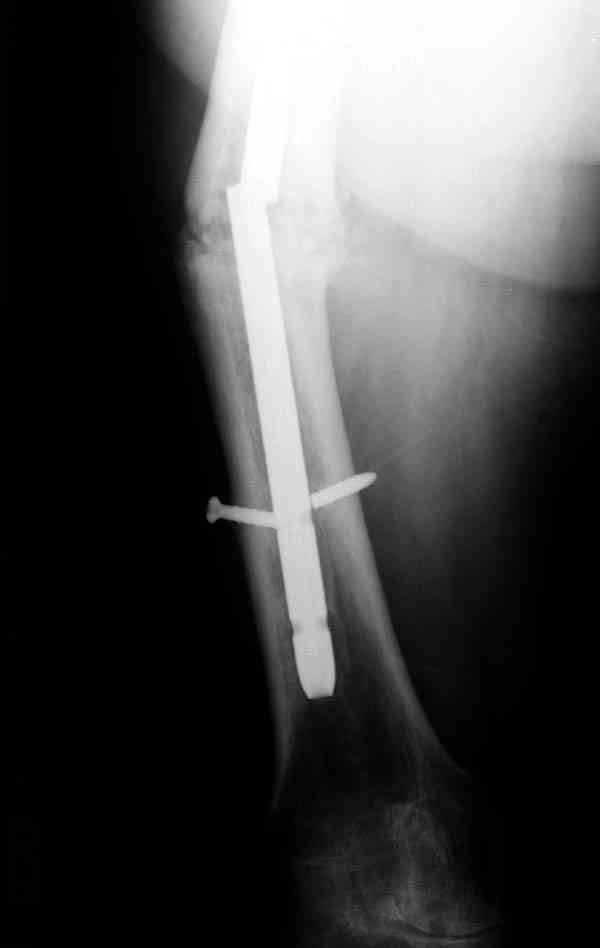

Сросшаяся малоберцовая как распорка привела к образованию ложного сустава. В таких случаях удаляем сломанный штифт и проводим стимуляцию ложного сустава рассверливанием. Рассверливание канала создает стимуляцию на месте ложного сустава, и динамический вариант блокировки штифта с большим диаметром создаст стабильность. Ранняя нагрузка после остеотомии малоберцовой приведет к сращению ложного сустава.

Приспособление для удаления сломанных штифтов и наличие ЭОП облегчит задачу. При отсутствии крючка тогда можно применить обычный длинный ball pointed guide wire от интрамедулярного набора. Проволока, пропущенная за пределы гвоздя и зажатая другая вытащат сломанный конец штифта без проблем.